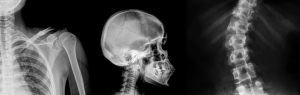

We are thrilled to announce the relaunch of our Image Interpretation eLearning course! Now packed with more features, updated content, and interactive learning experiences than ever before!

The course is both an advanced course for medical teams communicating X-Rays, and a guide that will give students with less experience an insight into the topics complexities. Join us on this educational journey and discover all the valuable insights and knowledge waiting for you.